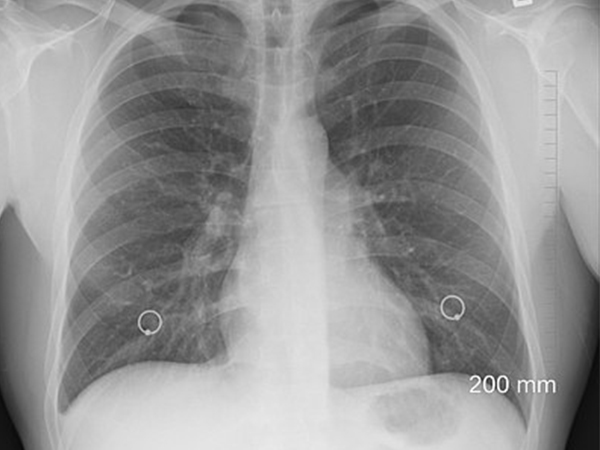

World Tuberculosis Day 2023: யாருக்கு நுரையீரல் காசநோய் வரும் அபாயம் உள்ளது? அதன் அறிகுறிகள் என்ன?

World Tuberculosis Day 2023: நம்மில் பலரும் டிபி என்னும் காசநோய் குறித்து அறிந்திருப்போம். இதன் அறிகுறிகள் மற்றும் சிகிச்சை பற்றி கேள்விப்பட்டிருப்போம். இது ஒரு நுரையீரல் சார்ந்த நோய் என்பதை அறிந்திருப்போம். ஆனால் இந்த நோய் நுரையீரலைக் கடந்து உடலின் மற்ற பகுதிகளையும் பாதிக்கும் என்பது நம்மில் பல பேர் அறியாத ஒரு விஷயமாகும்.

டிபி என்னும் காசநோய் ஒரு பொதுவான பெயர். ஆனால் நுரையீரல் காசநோய் என்பது சற்று புதிய பெயராகவே உள்ளது. இது ஒரு பரவக்கூடிய கிருமி தொற்றாகும். இது நுரையீரலில் தொடங்கி உடலின் மற்ற பகுதிகளுக்கும் பரவக்கூடியதாக உள்ளது. நுரையீரல் காசநோய் உருவாகக் காரணமாக இருக்கும் கிருமி மைக்கோபாக்டீரியம் ட்யூபர்க்ளோசிஸ் என்பதாகும். இந்த பாக்டீரியா, நுரையீரலை தாக்கும் போது இந்த பாதிப்பு உண்டாகிறது. ஆனால் உடலின் மற்ற பகுதிகளையும் பாதிக்கிறது.

* மார்பு எக்ஸ்ரே எடுக்க வேண்டும்